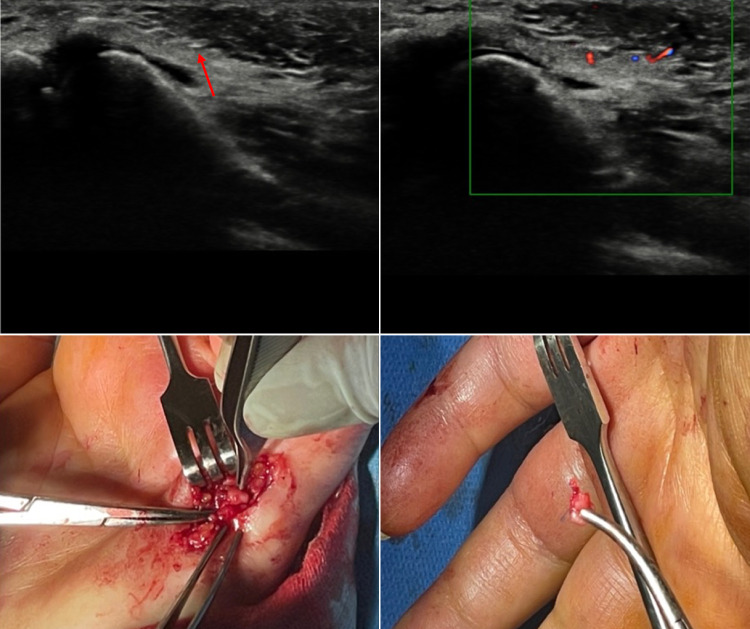

Fig. 1.

Case 1. A 39-year-old woman was admitted to our hospital because she had cut the palm of her left hand with a colored glass. She had tried to remove the small debris from the wound but later she began to experience paresthesia of the fifth finger of her left hand. US grayscale imaging was carried out where the patient felt pain and showed a small hyperechoic spot which could be observed with great difficulty at the level of the palmar surface of the hand close to the metacarpo-phalangeal joint of the fifth finger. CDUS was performed and TA indicated the presence and position of an FB. The patient experienced symptoms which limited the functionality of her hand, and she therefore underwent surgery. The surgeon removed an FB of about 3 mm near the palmar digital nerve